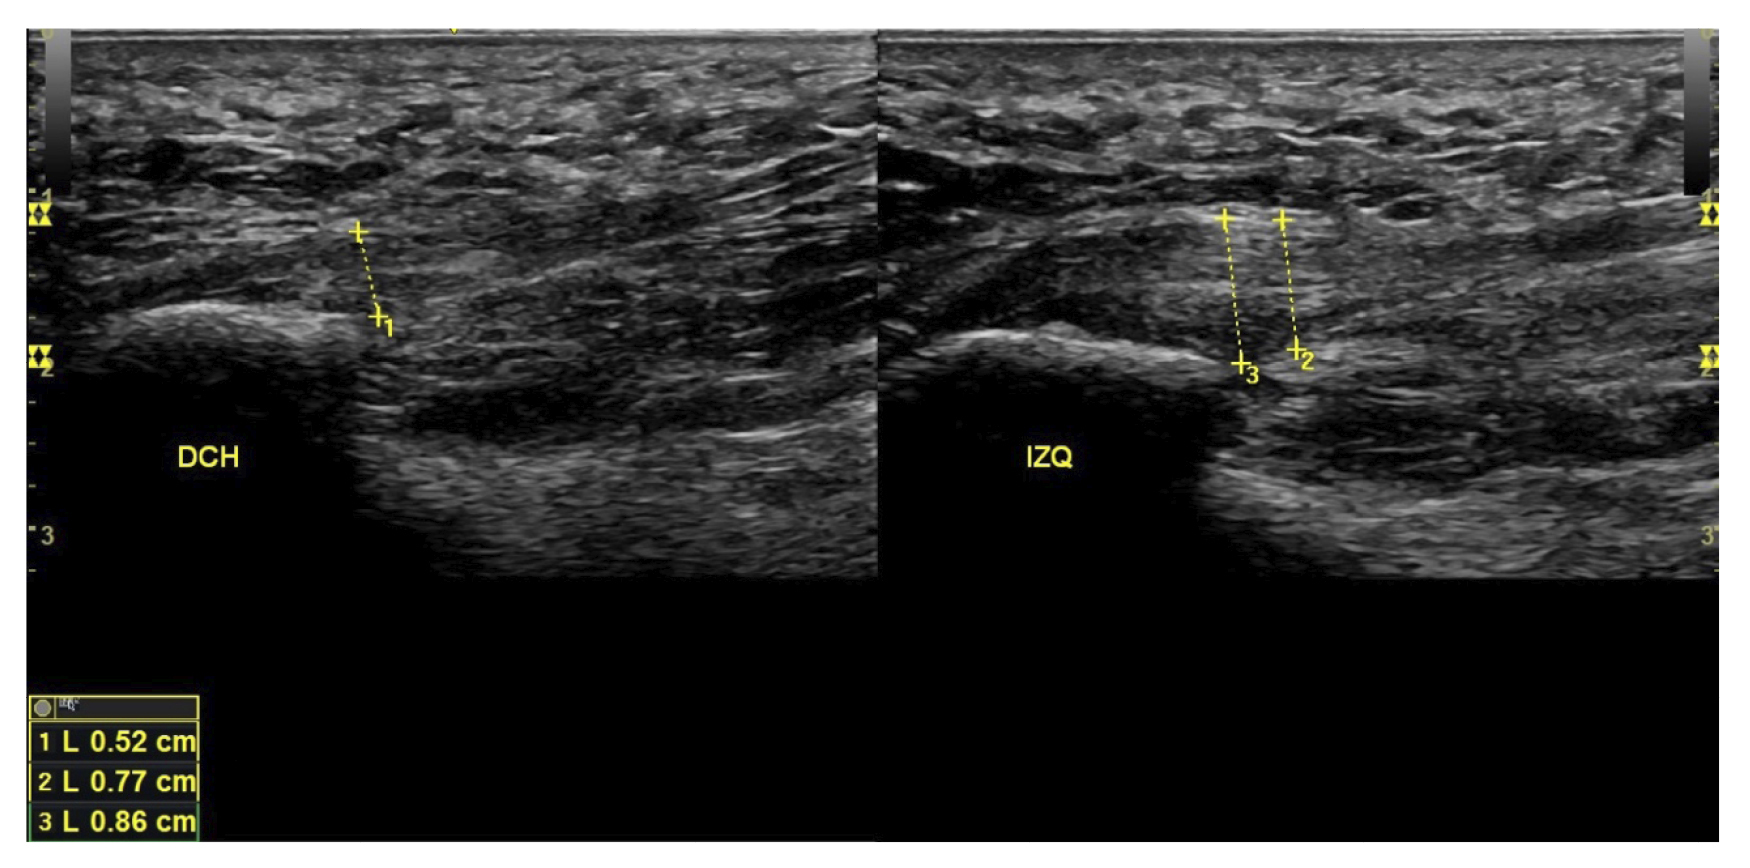

Figura 1. Fascia plantar con morfología normal a la izquierda y fascia plantar con morfología biconvexa a la derecha.

El diagnóstico se estableció en base a los síntomas y se confirmó mediante ecografía con equipo de alta resolución (Alpinion Ecube 9, ALPINION MEDICAL SYSTEMS Co., Ltd., República de Korea) con transductor lineal de 6 a 12 MHz (Figuras 2 y 3).

Figura 3. Área de medición del grosor de la fascia plantar. La línea punteada corresponde con la medición del grosor.